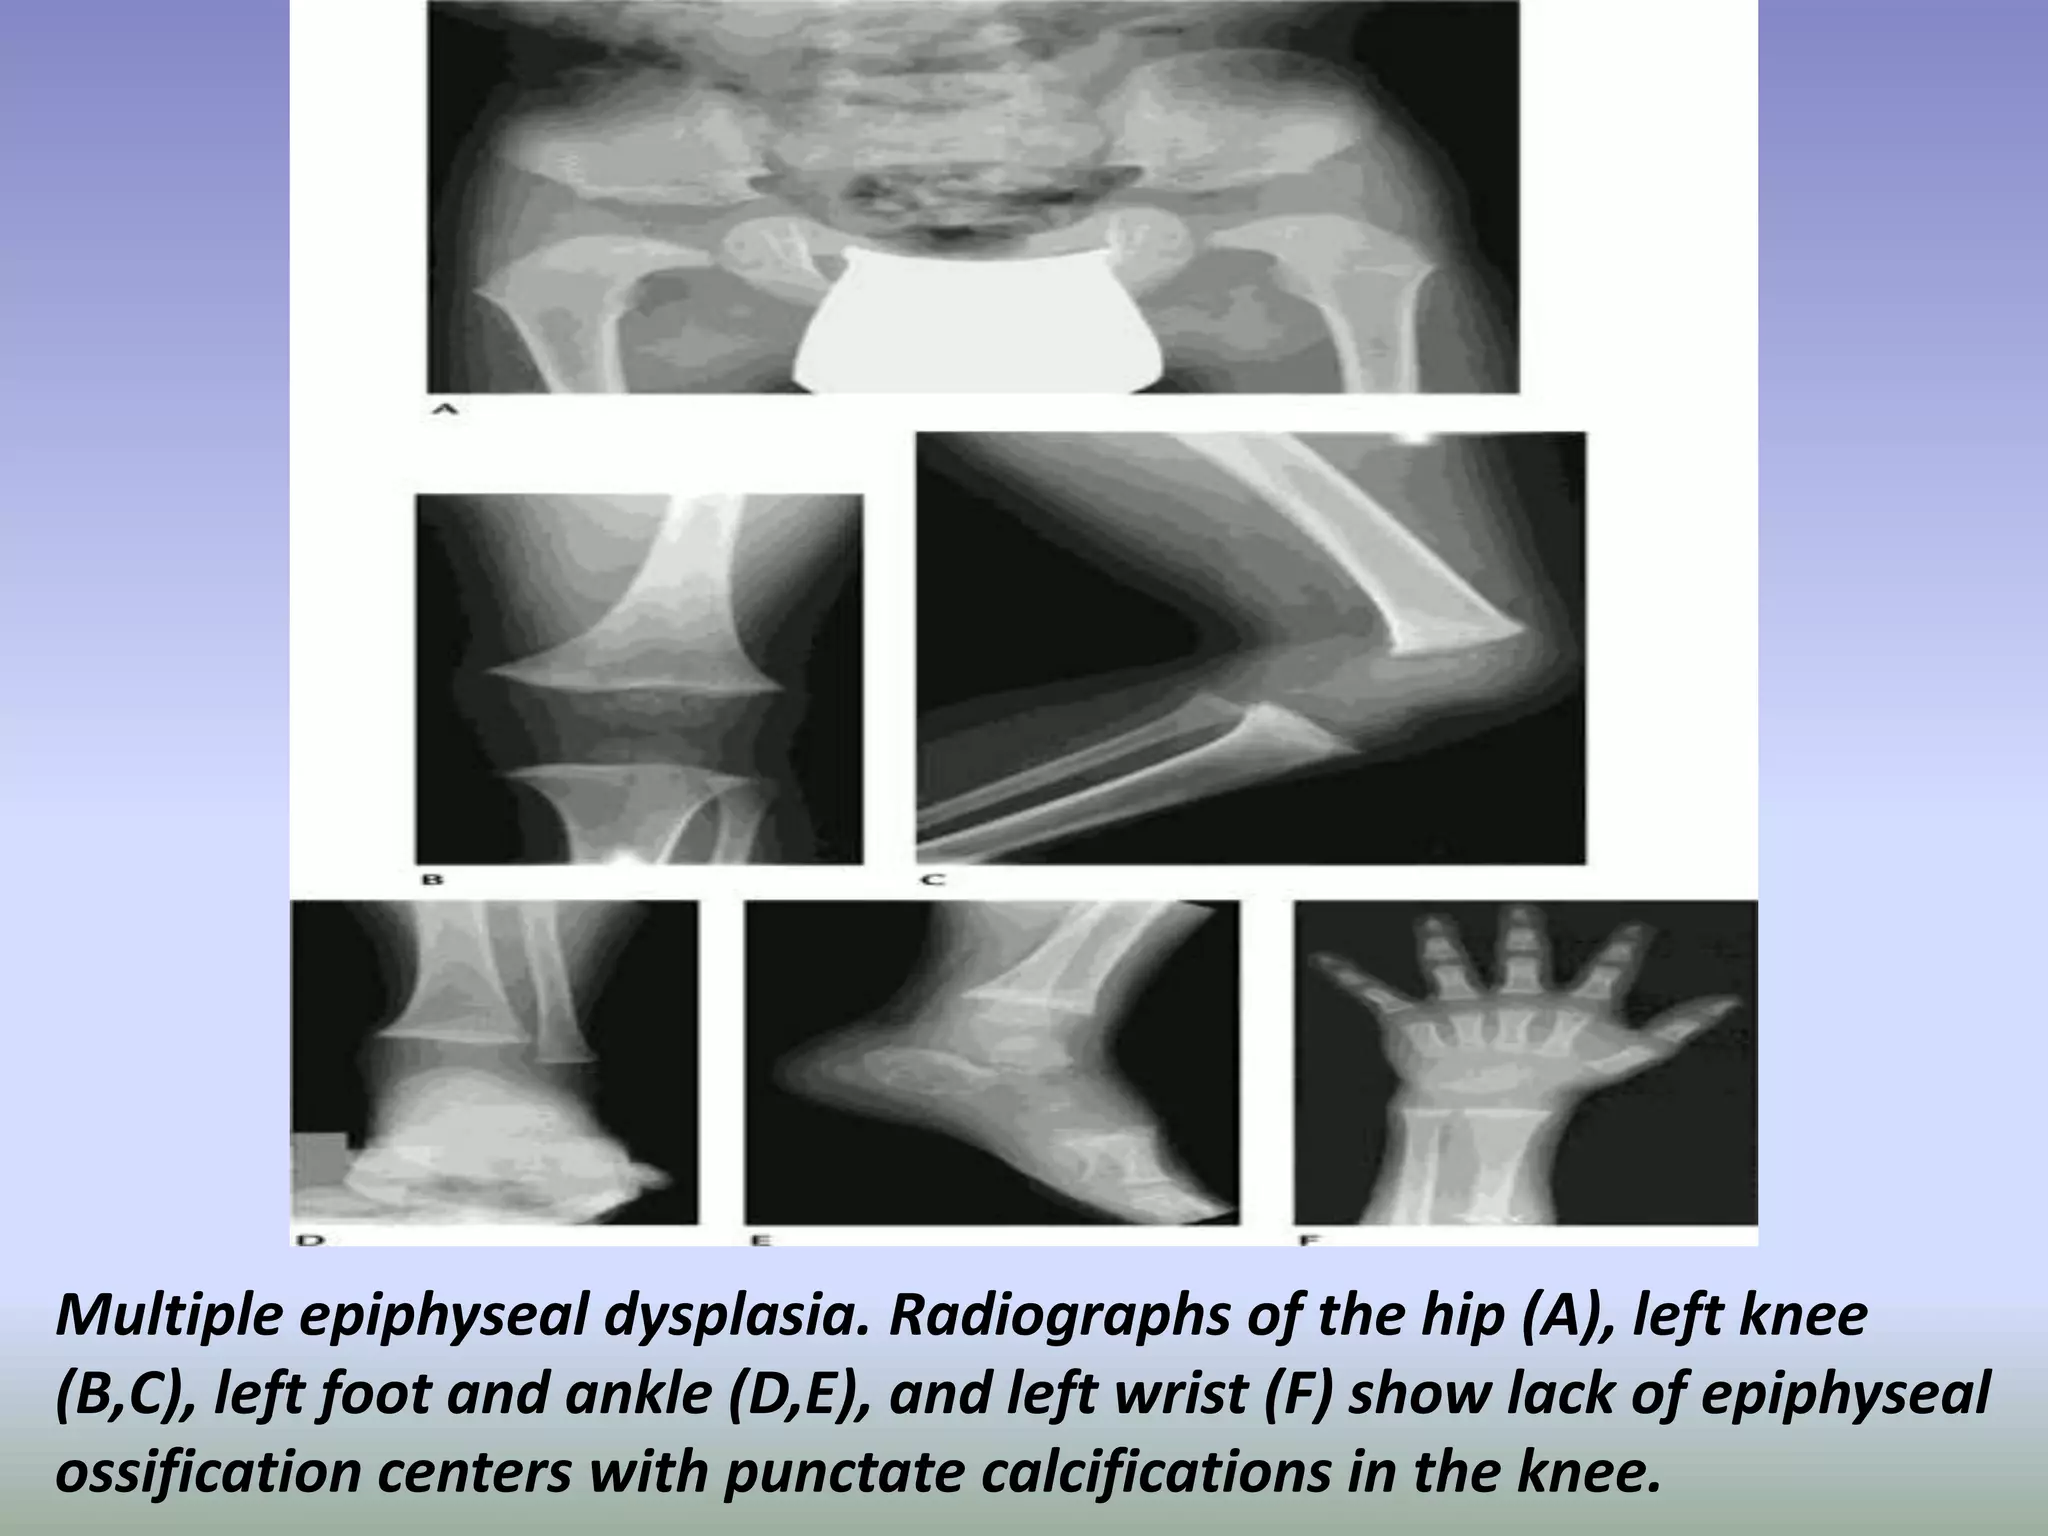

Multiple epiphyseal dysplasia. Radiographs of the hip (A), left knee

(B,C), left foot and ankle (D,E), and left wrist (F) show lack of epiphyseal

ossification centers with punctate calcifications in the knee.